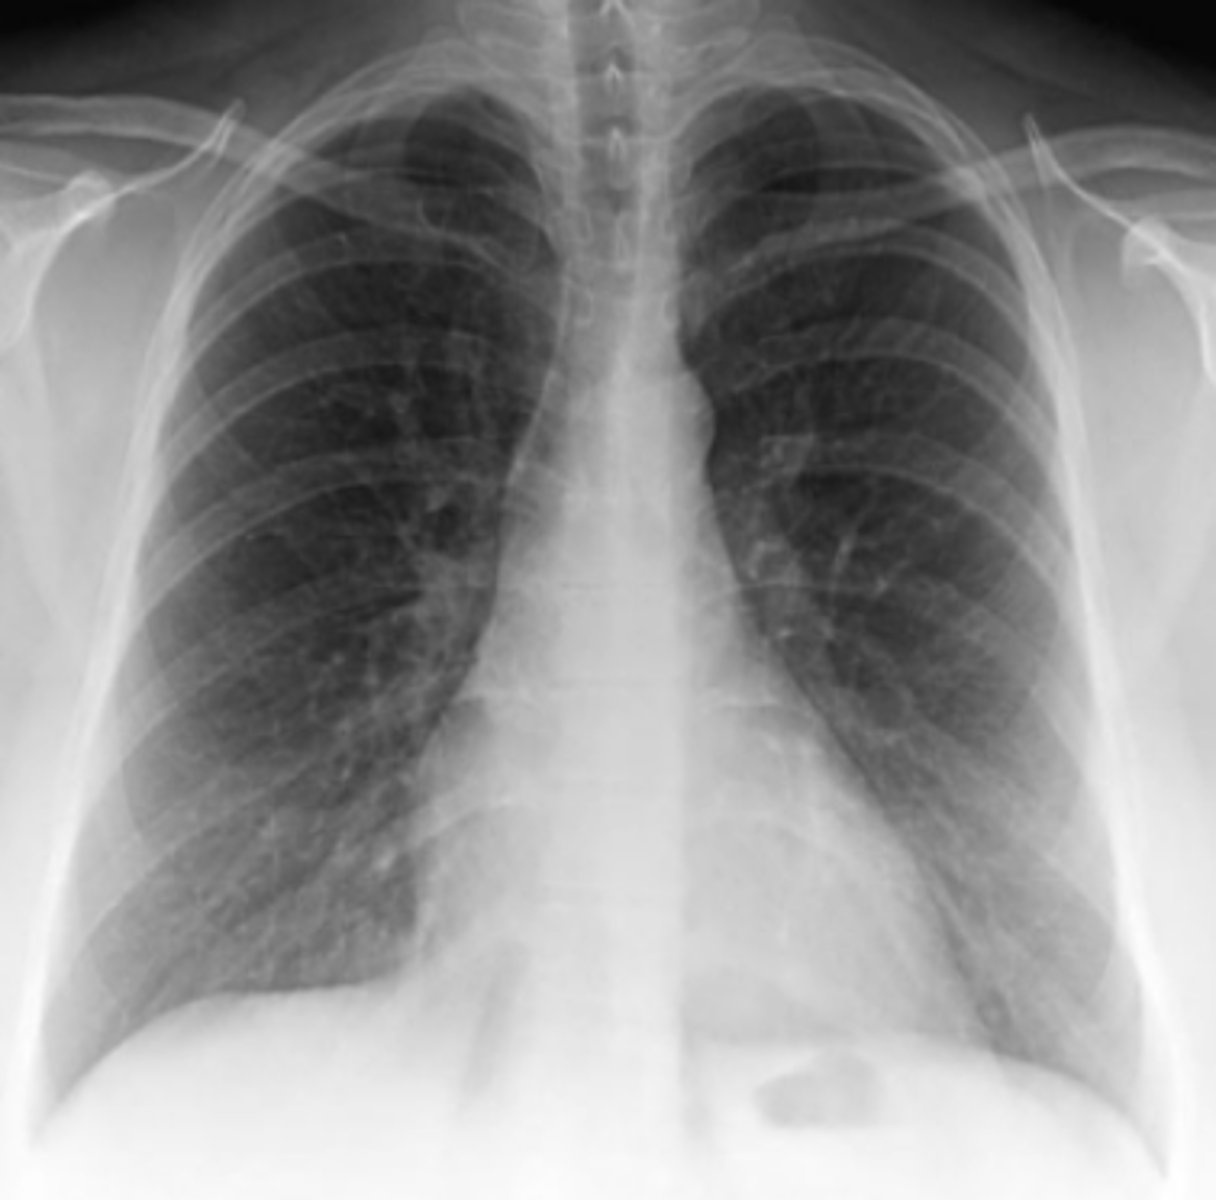

This chest radiograph was obtained to exclude pneumonia in a chronically ill 26-year-old woman (PA and lateral views of the chest).

For Case 6-12 (Figure 6-30), there is no evidence of

pneumonia, but there are several abnormalities that

are clues to the nature of this patient's chronic illness.

Which finding is such a clue?

A. The presence of a central venous line

B. Enlargement of the pulmonary artery segment of

the mediastinum

C. Depression in the endplates of numerous vertebrae

D. Asymmetry of the breast shadows

Answer

C.

Many vertebral bodies in the lateral view shaped like the letter H with central depressions in the superior and inferior end plates

What does this patient have in the previous question?

Sickle cell! When they clump together the sickled cells they can block blood vessels. She is having AVN due to this! The mottled appearance of the humeral heads is from AVN as seen in sickle cell anemia patients. Did you note as well her spleen is small? Splenic infarct is seen in these patients.